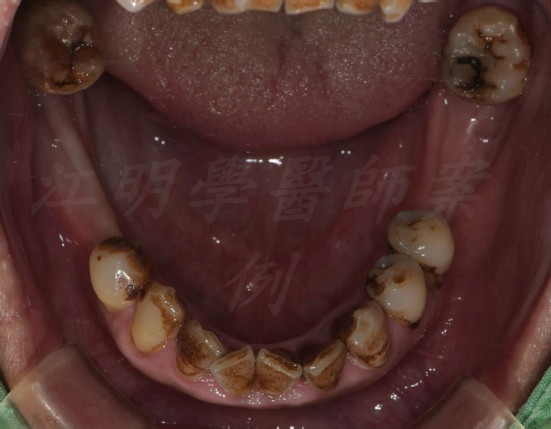

活動式假牙案例

牙齒狀況改善

治療前

治療後

這些照片展示了您的牙齒在術後得到顯著改善,排列更加整齊、美觀,並達到理想的咬合狀態。

也能增強口腔健康。